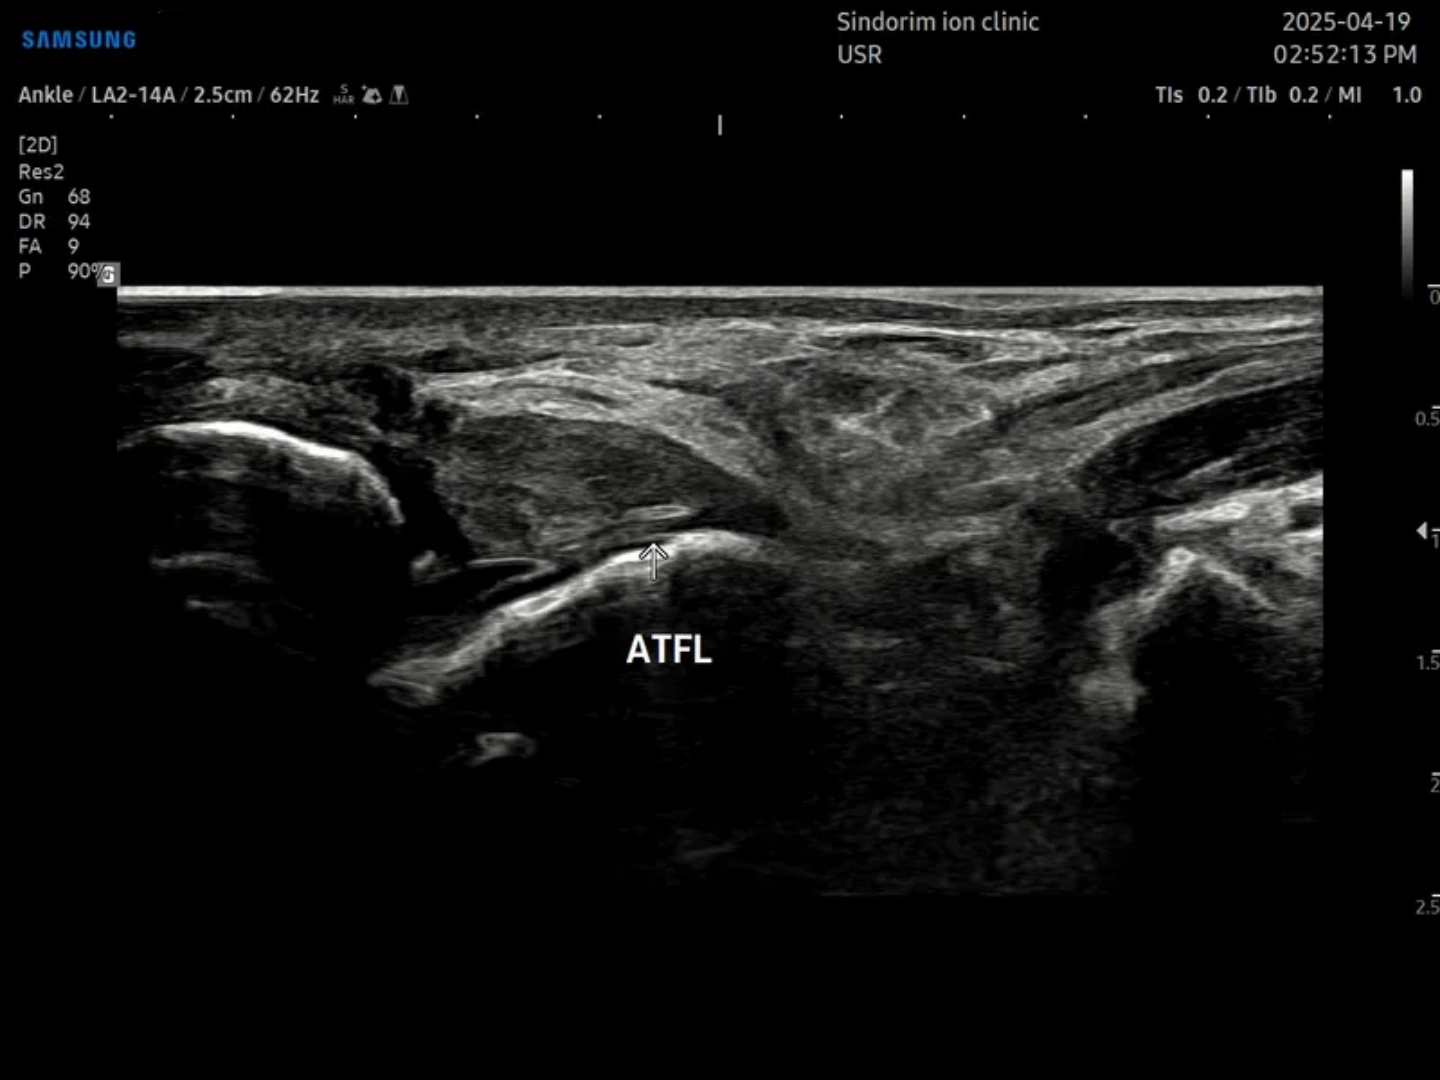

- 치료기간 : 25 . 4 . 19 ~ 25 . 9 . 0

- 치료횟수 : 20 회

치료 전

좌측: 비골근건 우측 ATFL

치료 후 : 비골근 건은 10회차에 마무리 / ATFL은 20회차에 마무리